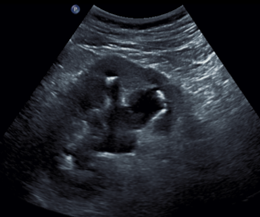

Abdomen aigu non traumatique - génito urinaire